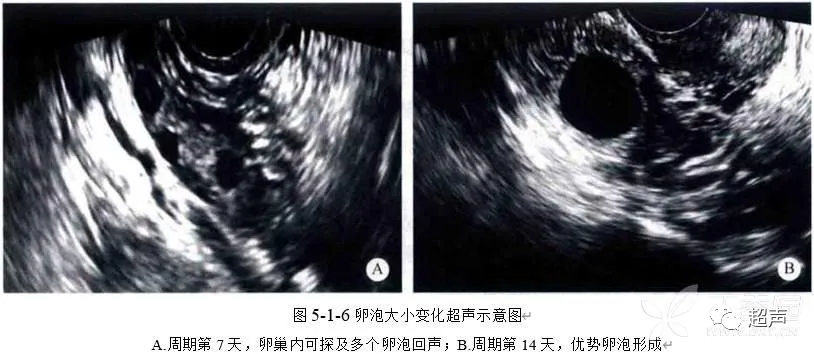

健康科普 | 好“孕”第一步——卵泡的超声监测